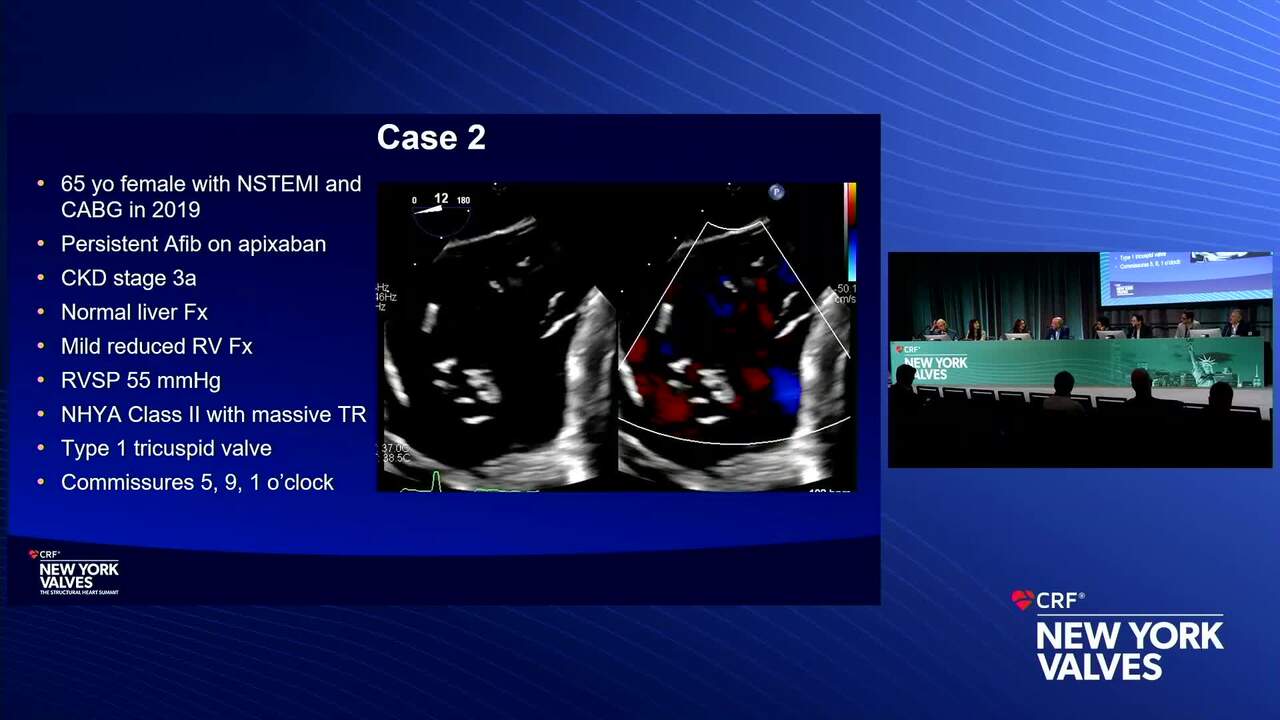

Case Presentation: Mitral and Tricuspid Valve Regurgitation

Case Discussion: Clinical Conundrums: Mitral and Tricuspid Valve Disease